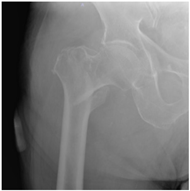

For X-ray 3, four scenarios were developed.![]() | Scenario 1: What would be your operation preference for a mobile patient aged 50–70 and with an ASA score of 1–2? Scenario 2: What would be your operation preference for a mobile patient aged 71 years or older with an ASA score of 1–2? Scenario 3: What would be your operation preference for a mobile patient aged 50–70 with an ASA score of 3–4? Scenario 4: What would be your operation preference for a mobile patient aged 71 years or older with an ASA score of 3–4? |